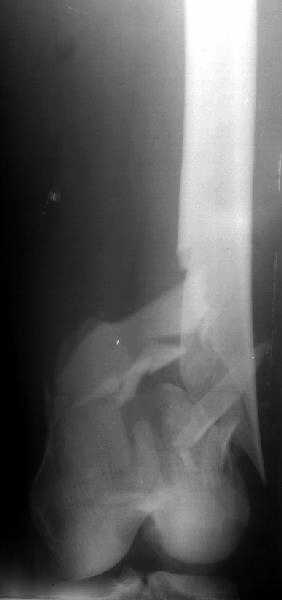

The mobilisation of knee is started immediately from the second day. Weight bearing is permitted as in any other interlocked nailing. That is, Toe touch to start with and within four days, partial to in another two weeks, full weight bearing. Of course that is assuming that the correct size nail has been used. Up to 70 kg body weight, 11no will be good enough and 12mm if more.Usually at the 1st followup, at 6 weeks time, they have full flexion..I

Enclosing a recent intraop picture